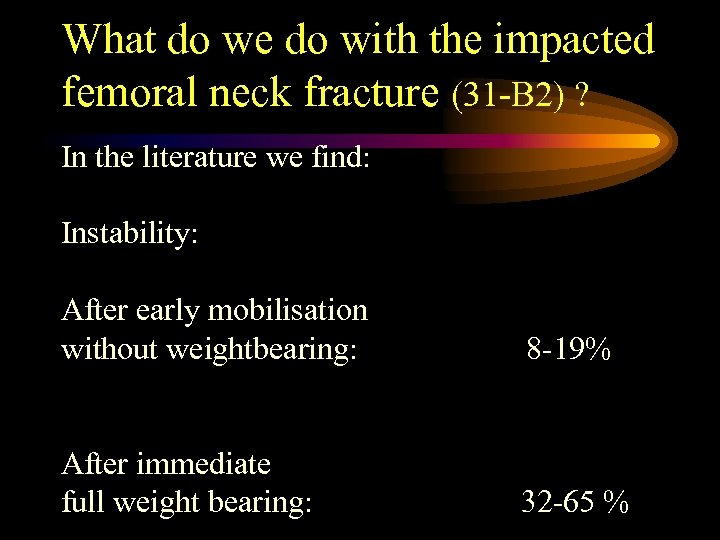

What do we do with the impacted femoral neck fracture (31 -B 2) ? In the literature we find: Instability: After early mobilisation without weightbearing: 8 -19% After immediate full weight bearing: 32 -65 %

What do we do with the impacted femoral neck fracture (31 -B 2) ? In the literature we find: Instability: After early mobilisation without weightbearing: 8 -19% After immediate full weight bearing: 32 -65 %